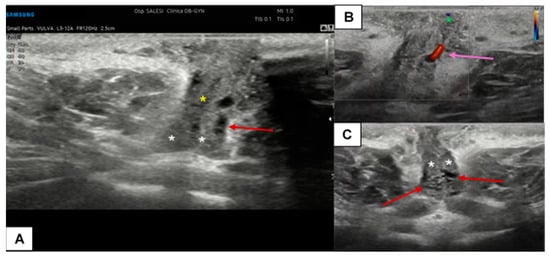

7.1. Benign Vulvar Lesions

7.2. Vulvar Dermatosis and Precancerous Lesions

7.3. Malignant Vulvar Lesions